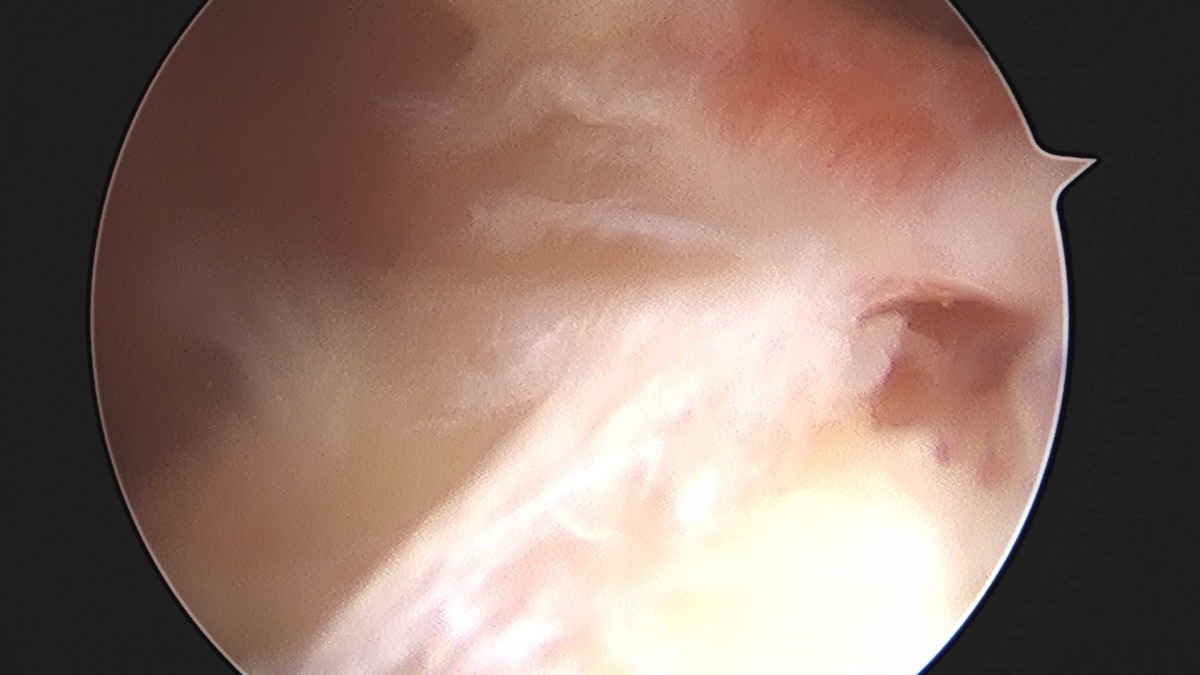

이재상원장님 어깨 견봉하 감압술 및 관절낭 이완술 음성O 환자

작성자 최고관리자 댓글 0건 조회 805회 작성일 25-09-16 15:32